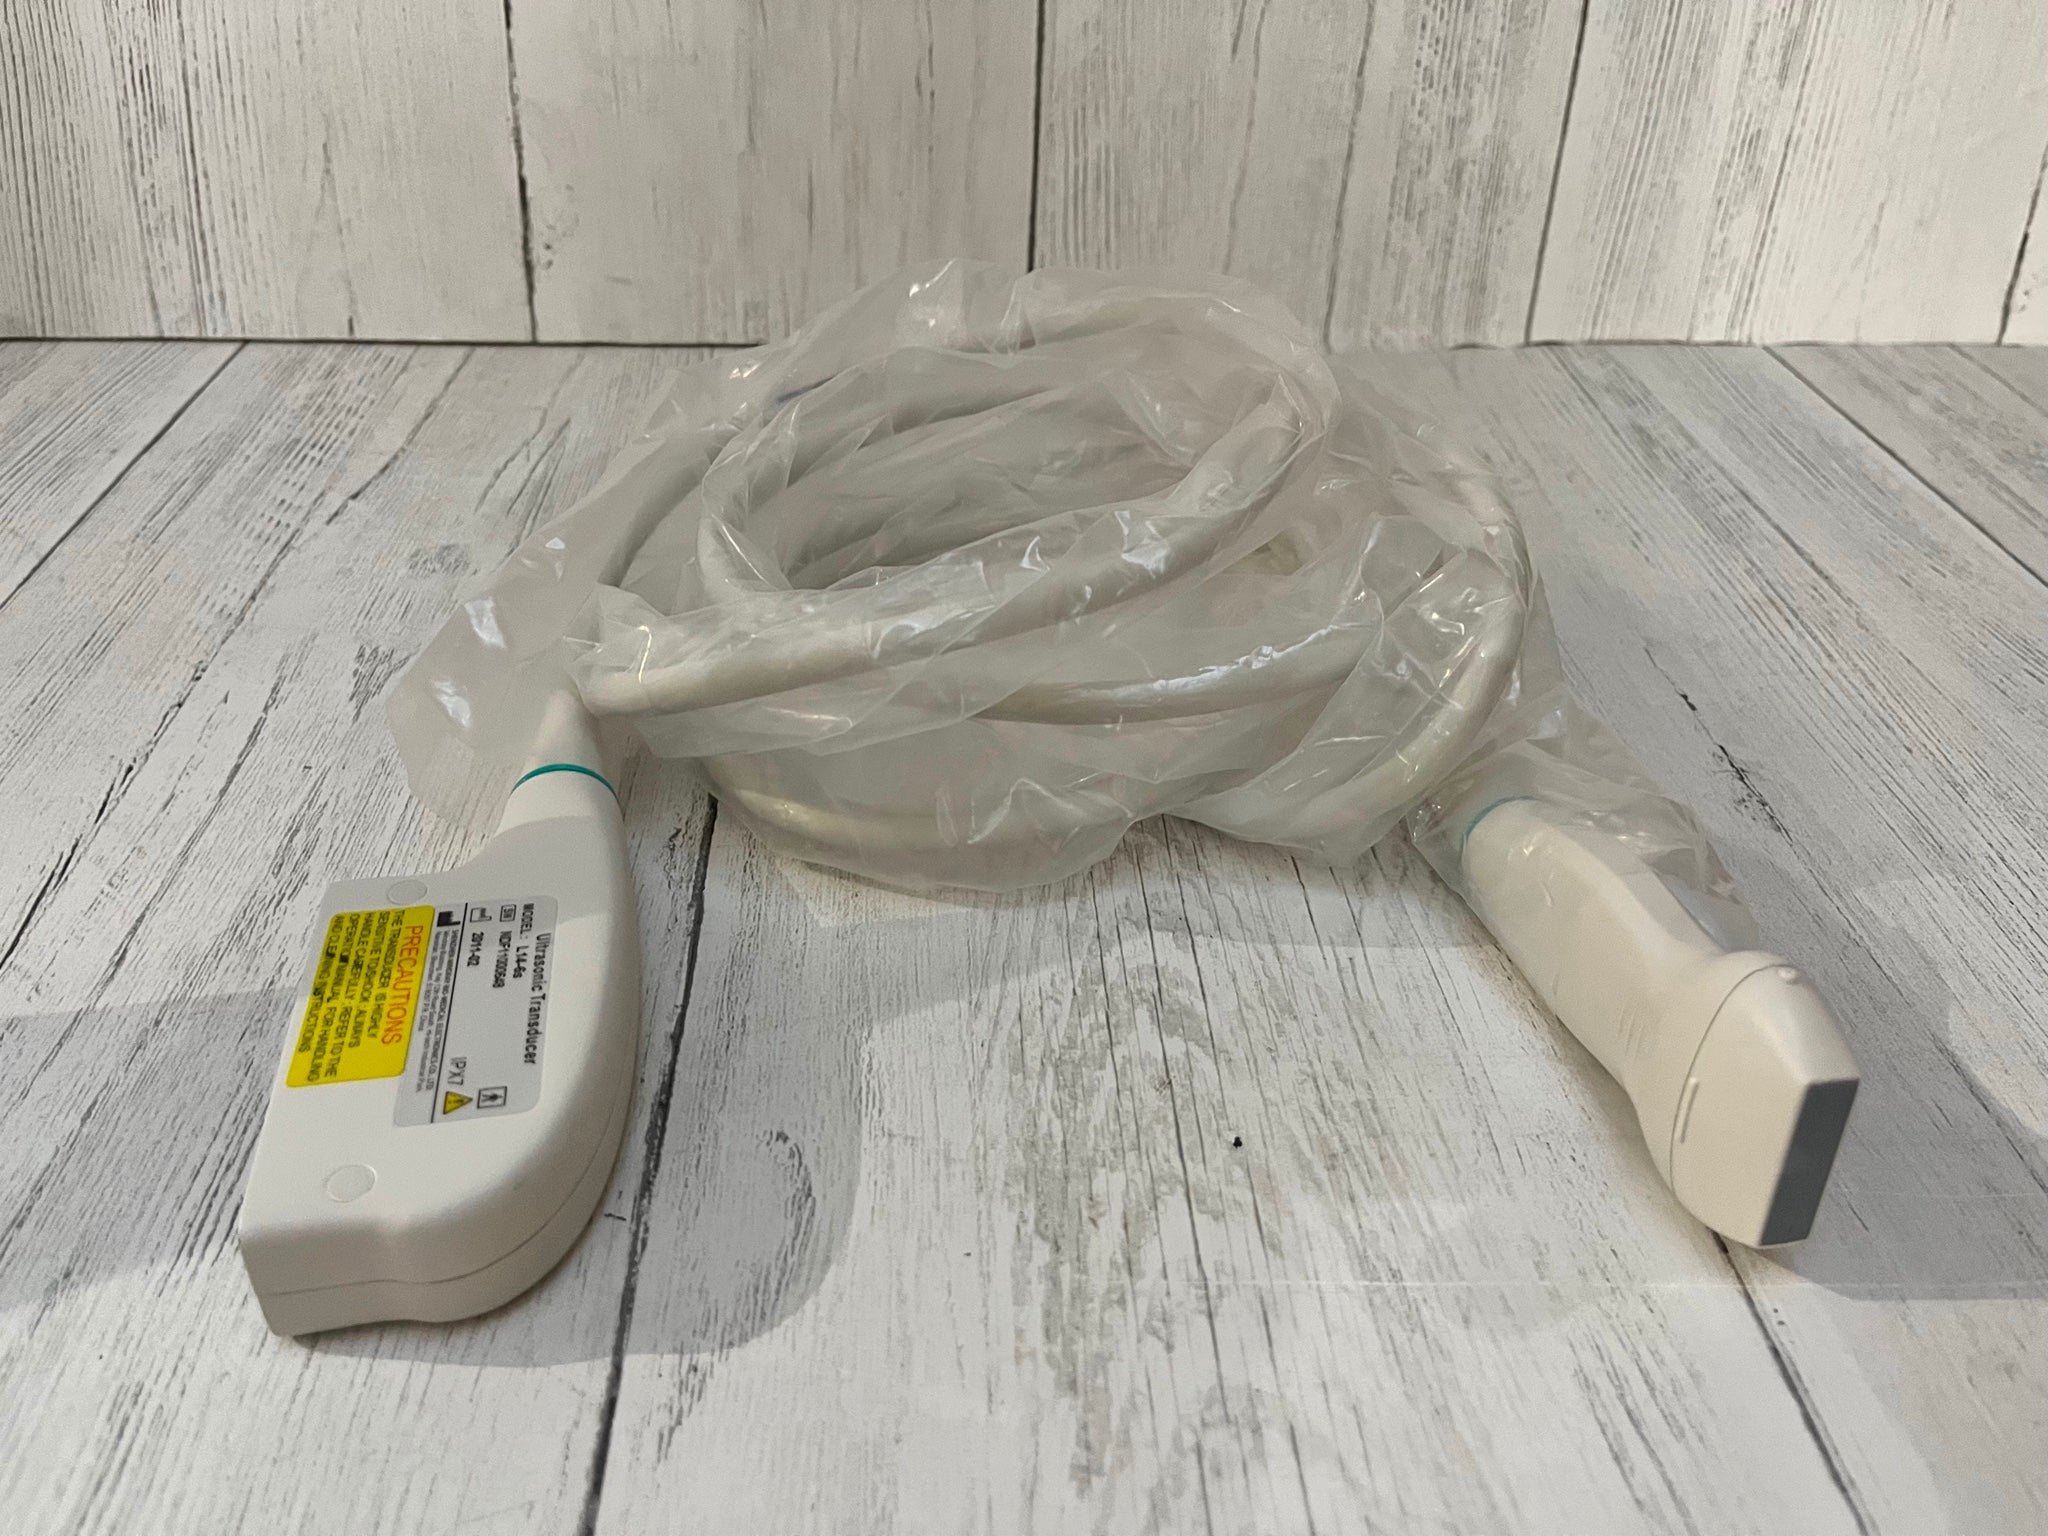

Description

Condition: Used: An item that has been used previously. The item may have some signs of cosmetic wear, but is fully operational and functions as intended. This item may be a floor model or store return that has been used. See the sellerâs listing for full details and description of any imperfections. See all condition definitions- opens in a new window or tab ... Read moreabout the condition

Brand: GE

Model: 4C-RS